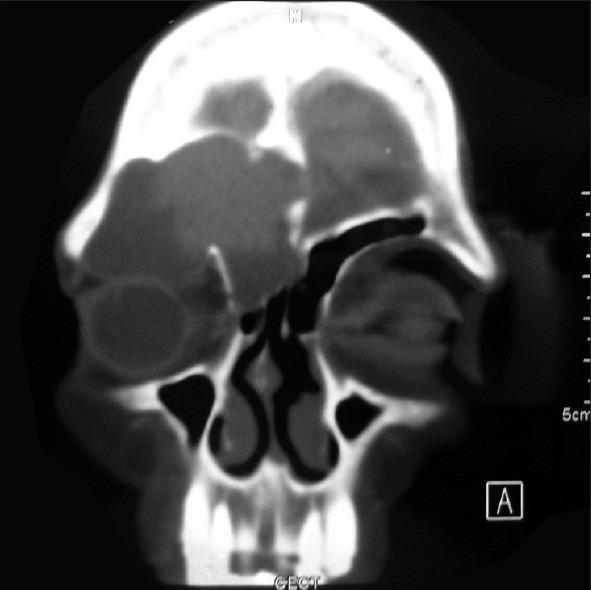

A mucocele of a para-nasal sinus is an accumulation of mucoid secretion and desqua-mated epithelium within the sinus with distension of its walls and is regarded as a cyst like expansile and destructive lesion. If the cyst invades the adjacent orbit and continues to expand within the orbital cavity, the mass may mimic the behavior of many benign growths primary in the orbit. The frontal sinus is most commonly involved, whereas sphenoid, ethmoid, and maxillary mucoceles are rare. Floor of frontal sinus is shared with the superior orbital wall which explains the early displacement of orbit in enlarging frontal mucoceles. Frontal sinus mucoceles are prone to recurrences if not managed adequately. Here, we are evaluating different approaches used to manage various stages of frontal mucoceles which presented to us with orbital complications. Three cases of frontal sinus mucocele are discussed which presented to our OPD with different clinical symptoms and all cases were managed by different surgical approaches according to their severity. We also concluded that it is prudent to collaborate with the neurosurgeons for adequate management of such complex mucoceles by a craniotomy approach.

鼻窦黏液囊肿是鼻窦内黏液样分泌物和脱落上皮的积聚,伴有鼻窦壁扩张,被视为一种类似囊肿的膨胀性破坏性病变。如果囊肿侵犯相邻眼眶并在眶腔内持续扩大,肿块可能类似许多眼眶原发性良性肿瘤的表现。额窦最常受累,而蝶窦、筛窦和上颌窦黏液囊肿罕见。额窦底部与眶上壁相邻,这解释了额窦黏液囊肿增大时眼眶早期移位的原因。如果处理不当,额窦黏液囊肿容易复发。在此,我们评估了用于处理出现眼眶并发症的不同阶段额窦黏液囊肿的不同方法。讨论了3例因不同临床症状就诊于我们门诊的额窦黏液囊肿病例,所有病例均根据其严重程度采用不同的手术方法进行处理。我们还得出结论,对于此类复杂黏液囊肿,通过开颅手术方法进行充分处理时,与神经外科医生合作是明智的。